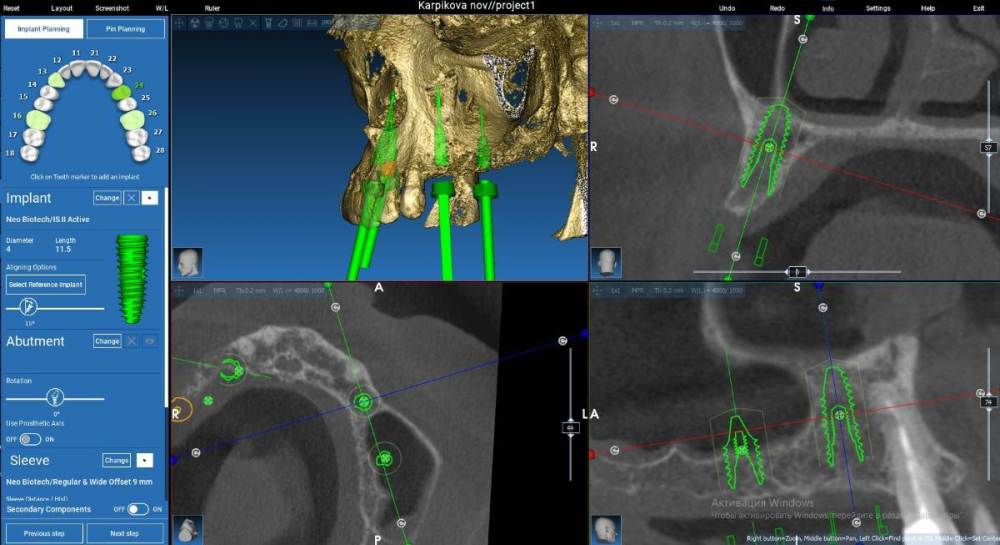

Fin Опубликовано 2 августа, 2022 Поделиться Опубликовано 2 августа, 2022 (изменено) Здравствуйте коллеги. Очень нужен ваш совет с планом лечения. Планирую установить 4 импланта на В.Ч.. В области зубов 2.4 и 2.6 все более менее понятно( 2.4 просто ставить а 2.6 ОСЛ и ставить), а вот в 1 сегменте все значительно сложнее. На данный момент имею три варианта конечно все варианты с навигационным шаблоном: 1.) 1.3 +НКР титановой сеткой (смущает что восстанавливать надо небно) 1.5 под углом и протезом на МЮ с небольшой консолью 1.6 (в виде премоляра) 2. 1.3 все так же либо рискнуть и оставить пару витков открытыми 1.5 имплант 4х10(11,5) и 1.7- 4х 7,3 с ЗСЛ 3 . Может Все таки пора начинать ставить анкилоз и поставить в обл 1.3 3,5х8 с небольшим оголением небной стенки.В остальный местах на этой стороне так же ануилоз. Протезрование делать с уровня МЮ. Благодарю Вас за советы. Скрины 2 сегмента Изменено 2 августа, 2022 пользователем Fin Ссылка на комментарий

Fin Опубликовано 2 августа, 2022 Автор Поделиться Опубликовано 2 августа, 2022 (изменено) 15 минут назад, Irouil сказал: В первом варианте у вас 1.3 выходит куда-то практически в 1.4, имхо надо чуть медиальнее Я бы не стал там титановую сетку городить, небо - это фактически трехстеночный дефект, сделал бы сосидж вокруг тонкого ФДМ или временной коронки А с остальными винтами почему не открытый синус+импланты? Ну или если заходит закрытый под углом (не очень понятно по скринам), то его + МЮ (и тогда у 1.3 сосидж вокруг мульта) Спасибо за ответ. На счет 1.3 вы правы, надо медиальнее, нечаянно выровнял оси имплантов. Вы немного не поняли. Думал поставить 1.5 под углом и на него кослольку небольшую до 6 ки. Да, возможно ОСЛ в области 1,6 будет правильнее и в последующем имплант будут правильнее. Изменено 2 августа, 2022 пользователем Fin Ссылка на комментарий

АнтонТЛТ Опубликовано 2 августа, 2022 Поделиться Опубликовано 2 августа, 2022 Меня одного смущает слишком небное положение 13? Ссылка на комментарий

Fin Опубликовано 2 августа, 2022 Автор Поделиться Опубликовано 2 августа, 2022 (изменено) 1 час назад, АнтонТЛТ сказал: @Fin сделайте расстановку зубов, исходите из положения ортопедического, а не условий костной ткани Вы правы...Быстро сделал виртуально постановку, нужно наращивать с обеих сторон получается Изменено 2 августа, 2022 пользователем Fin Ссылка на комментарий